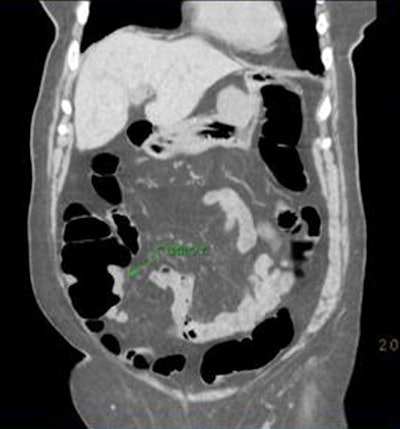

![]() |

| CTC in a 78-year-old woman with incomplete colonoscopy demonstrates cecal carcinoma. All images courtesy of Dr. Hanna Zafar and Dr. Anna Lev-Toaff. |